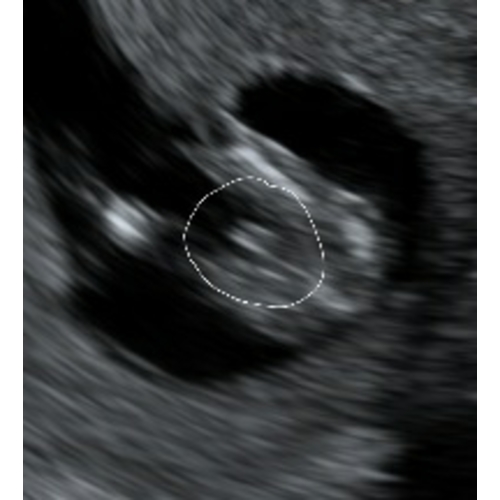

Je ziet 3 streepjes.. dat zijn de schaamlippen met in t midden de clitoris. Kan echt niet missen.

Kan echt niet missen is wel heel gedurft om te zeggen. TS is pas 13.3 en de fout wordt op dit termijn nog heel vaak gemaakt.

Ik zeg meisje. Maar het lijkt ook een beetje alsof de foto een beetje bewogen is